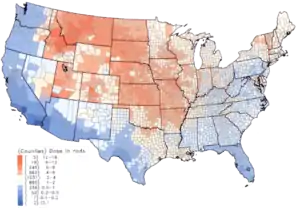

Within the US, the highest 131I fallout doses occurred during the 1950s and early 1960s to children having consumed fresh milk from sources contaminated as the result of above-ground testing of nuclear weapons.[6] The National Cancer Institute provides additional information on the health effects from exposure to 131I in fallout,[19] as well as individualized estimates, for those born before 1971, for each of the 3070 counties in the USA. The calculations are taken from data collected regarding fallout from the nuclear weapons tests conducted at the Nevada Test Site.[20]